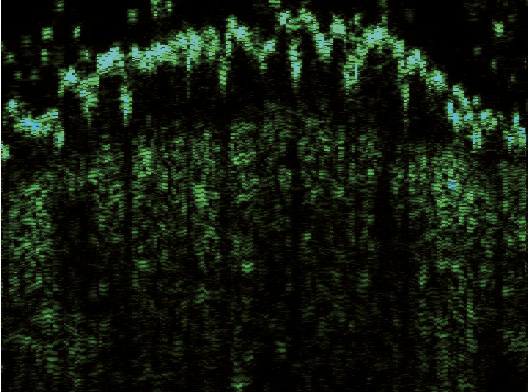

Эпидермис в очагах ББ определялся в виде полосы высокой эхогенности белого цвета с многочисленными желтыми и синими вкраплениями и в виде полосы зеленого оттенка, расположенной под ней. Его внутренний контур был четким и хорошо отграниченным от подлежащей дермы. В зависимости от ультрасонографической картины эпидермиса сканограммы очагов ББ были разделены на две разновидности. В 6 (75%) случаях (1-я разновидность) очаги представляли собой гиперэхогенную полосу неравномерной толщины, волнообразной формы с почкообразными отростками вглубь дермы (рис. 2). В 2 (25%) случаях (2-я разновидность) регистрировали гиперэхогенный слой одинаковой ширины на всем протяжении, с ровным внешним и внутренним контуром (рис. 3).

Рис. 2. Сканограмма болезни Боуэна (датчик 75 МГц). Гиперэхогенный эпидермис неравномерной толщины и волнообразной формы с почкообразными отростками вглубь дермы (разновидность 1). Гипоэхогенная зона определяется в виде образования полосовидной формы с четкими границами

Дерма имела четкое отграничение от подкожно-жировой клетчатки и равномерную ширину, В ней определялись гипоэхогенные образования, расположенные непосредственно под эпидермисом, полосовидной или округлой формы, диффузно-неоднородной структуры. Четкие контуры отмечались в 6 случаях (75%) и размытые – в 2 (25%). При этом полосовидная форма встречалась в очагах 1-й разновидности (см. рис. 2), а округлая – 2-й (см. рис. 3). Средние значения толщины эпидермиса, дермы в очагах поражения и коллатеральных участках, а также глубины распространения гипоэхогенных зон приведены в таблице.

При высокочастотном ультразвуковом сканировании отмечалось статистически значимое увеличение средней ширины эпидермиса в очагах ББ по сравнению с контрлатеральными, визуально неизмененными участками кожи (р < 0,05). Визуализировалось две его разновидности – волнообразная с почкообразными отростками вглубь дермы и в виде равномерной полосы, обе имели четкий внутренний контур.